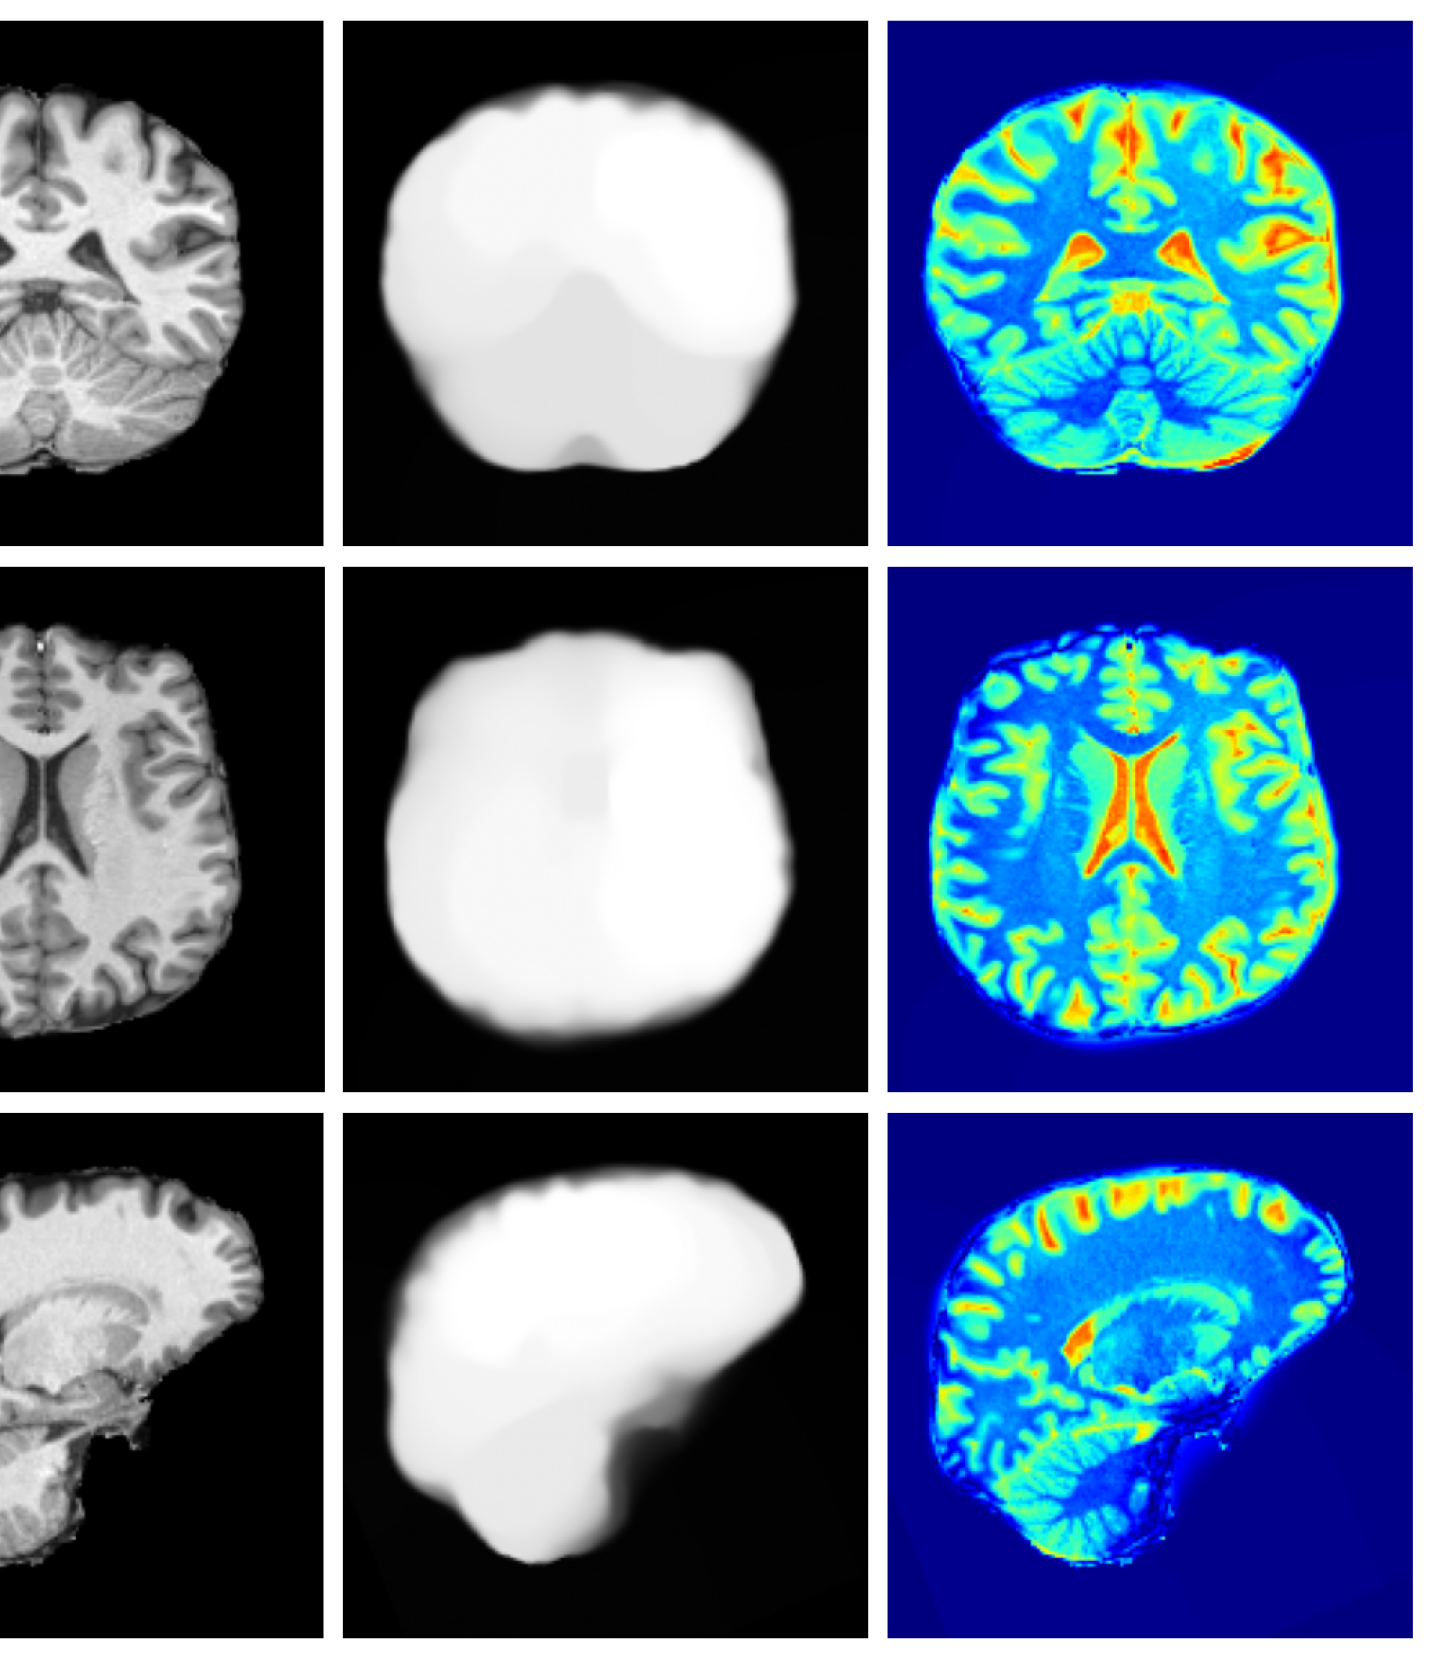

The image refinement results (see Appendix A.10 for more examples) in Figure 4 highlight our framework’s ability to enhance outputs from existing methods. While SynthSR can inpaint disease regions, the resulting tissue often appears unrealistic. Our method further refines these areas, producing anatomically plausible reconstructions with more realistic surface structures.